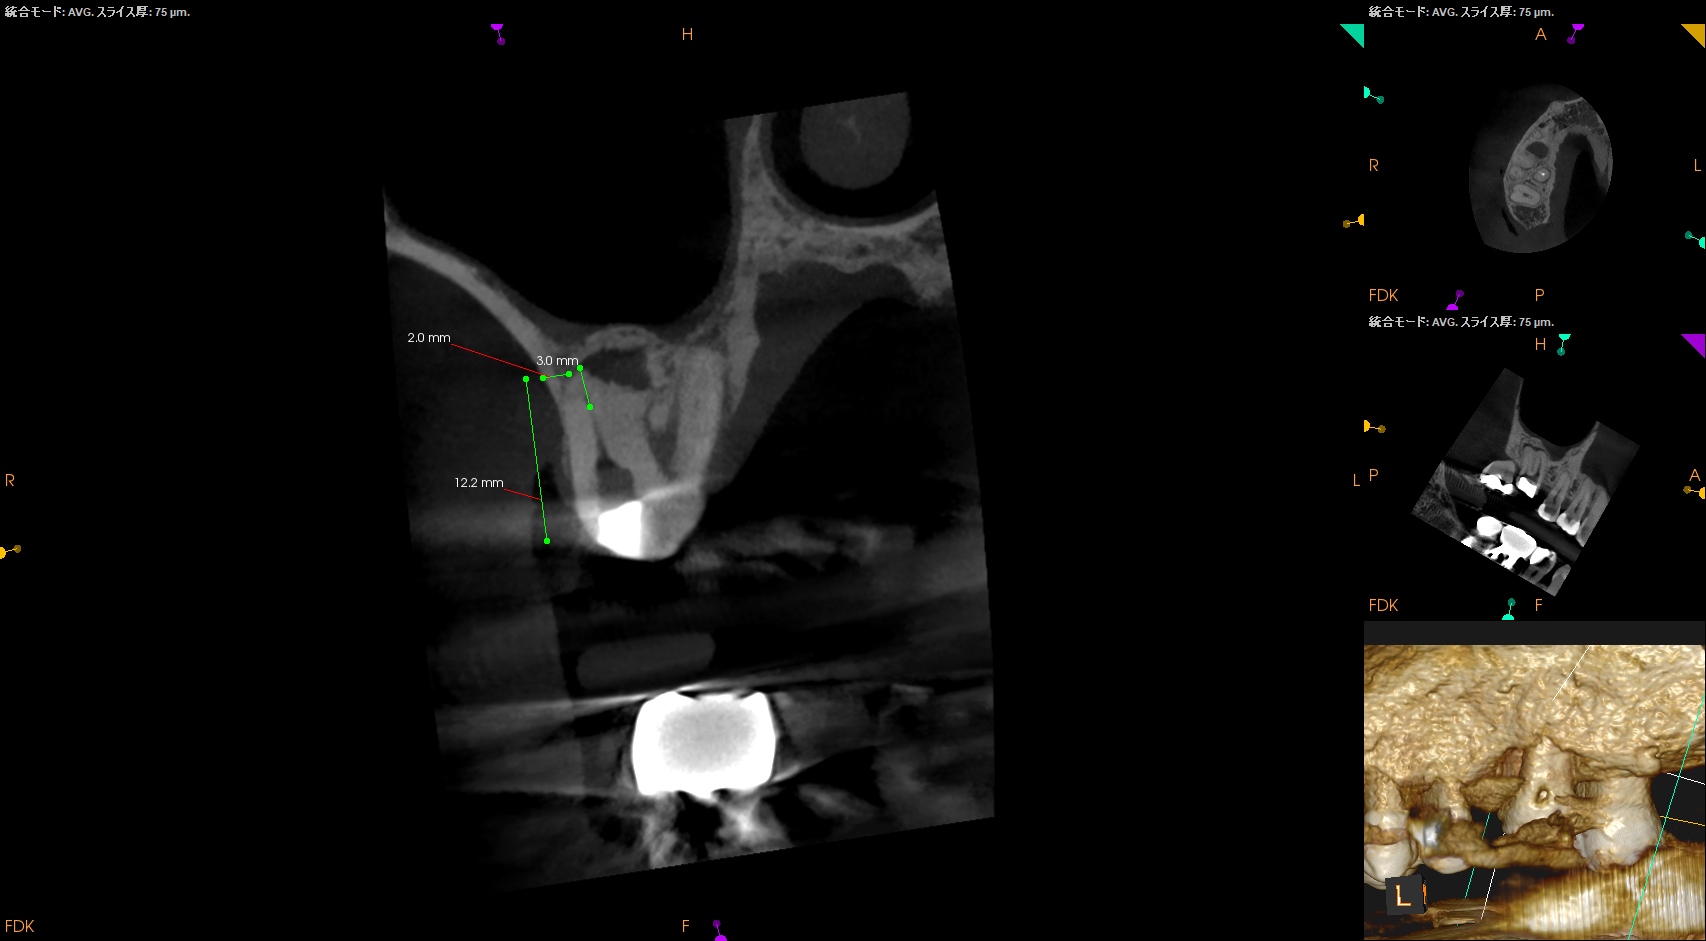

MB,DBのApicoectomyは

MB

CEJよりも12mm下方にMBのApexがあり、

そこを3mm切断するには6.4mmの切断幅が必要である。

そしてMB1-MB2を往復でPrepする必要があり、やや煩雑だ。

中程度の難易度だろう。